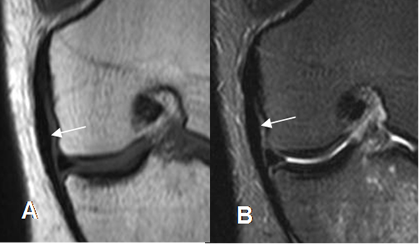

En las lesiones crónicas, se aprecia engrosamiento por fibrosis y pérdida de la grasa entre los fascículos. (3). (Fig 121).

Fig 121. Fibrosis del LCM.

A: RM coronal en T1 y B: RM coronal en STIR. El LCM se aprecia engrosado, aunque conserva su señal, por fibrosis residual.